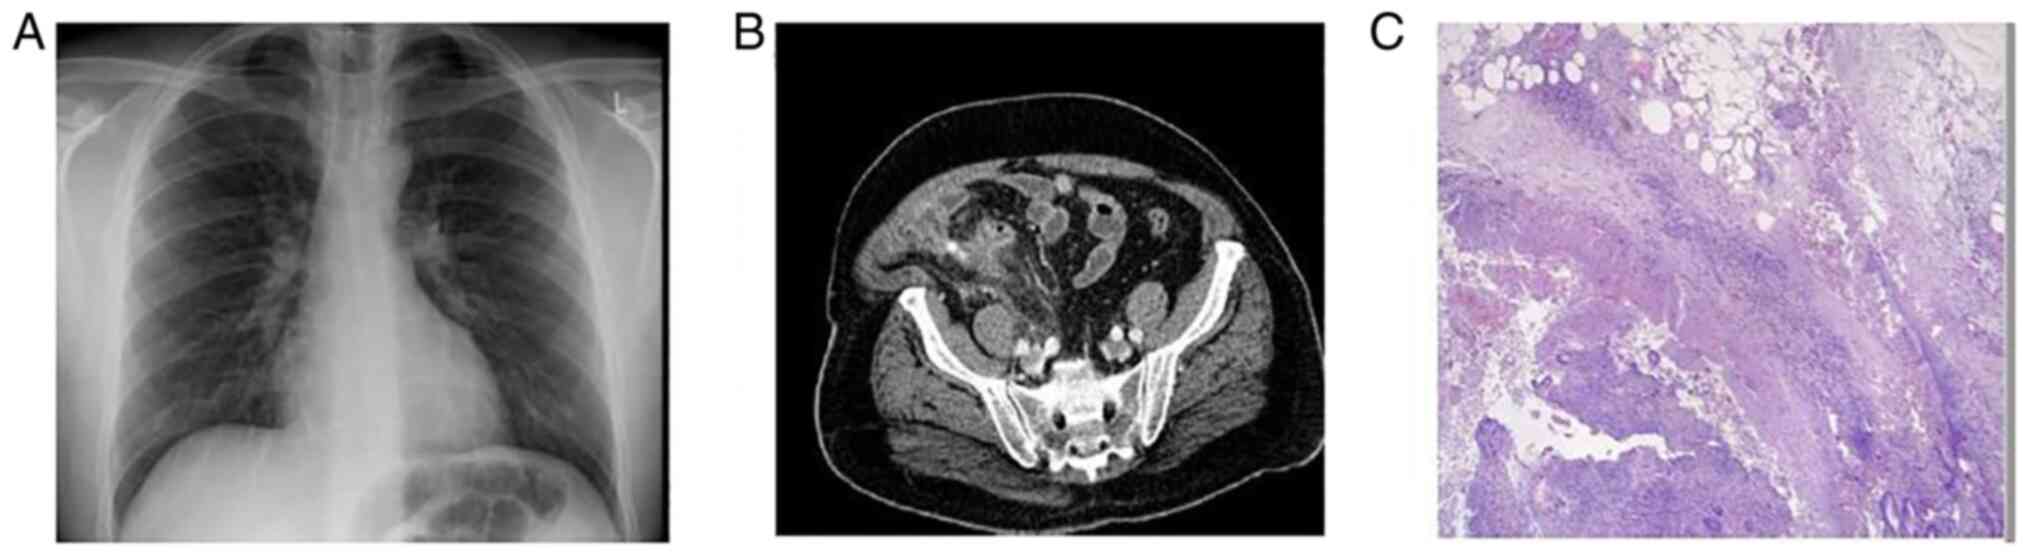

Figure 2

Case 2. (A) A chest X-ray revealed mild infiltrates in both lower lung lobes. (B) Abdominal computed tomography revealed mild dilation of the appendix and wall thickening. (C) Hematoxylin and eosin staining; original magnification, x200. The histological analysis revealed acute appendicitis with peri-appendicitis, as well as torsion of an epiploic appendix, with fibrosis in its wall and peripheral deposition of calcium salts. (D) A chest X-ray revealed infiltrates in all lung fields.

The patient received intravenous antibiotic therapy with cefoxitine at 1 g three times daily and metronidazole at 500 mg three times daily. His clinical condition gradually improved. The post-operative follow-up was uneventful and the patient was transferred to the COVID-19 unit for further management. On the third post-operative day, the patient presented with dyspnea and respiratory deterioration with an oxygen saturation of 92% in room air. A new arterial bloοd gas analysis revealed a pO2 of 61 mmHg, a pCO2 of 33 mmHg, pH 7.49 and HCO3 25.1 mmol/l in room air. A new chest radiograph revealed worsening infiltrates (Fig. 2D). The patient received therapy with intravenous dexamethasone at 6 mg once daily and remdesivir at 200 mg on the first day, followed by 100 mg daily for the following 4 days. He also received oxygen therapy with a nasal cannula delivering oxygen at a rate of 3 l/min. His clinical condition and oxygen levels gradually improved. No other complications occurred, and the patient was discharged following a 9-day hospitalization.